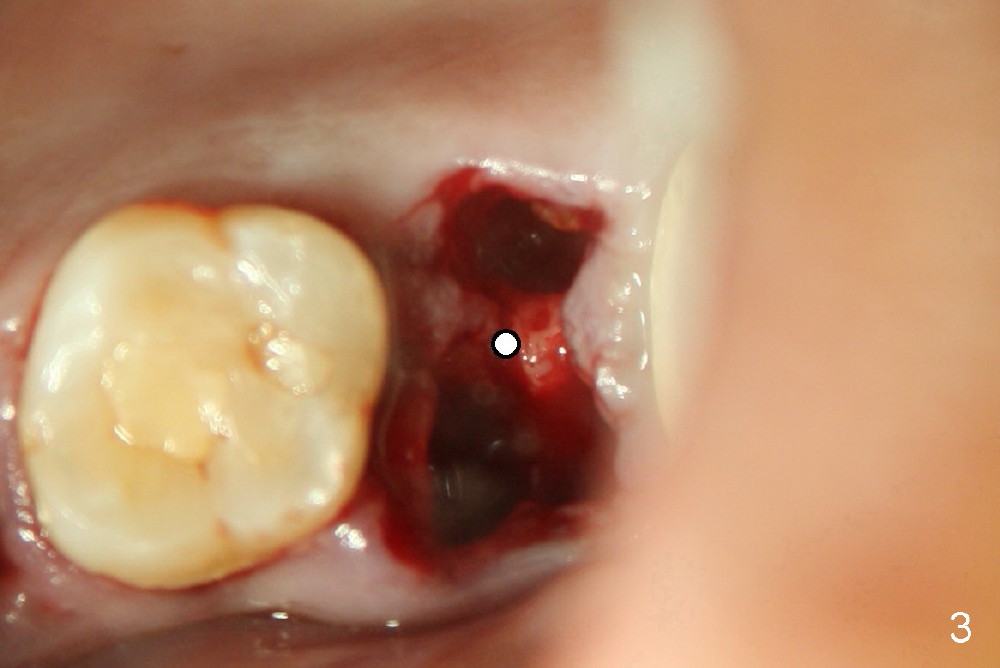

A 43-year-old lady has multiple nonsalvageable teeth. The first surgery involves two immediate implants in the upper left sextant (Fig.1: #13 and 15). The tooth #15 has 3 residual roots (MB, DB, P). There is no septum left between the first two roots when the tooth is extracted. A septum exists between the palatal (P) and buccal (B) sockets (Fig.2). Bone expansion technique is utilized to create an osteotomy in the septum. However, the smallest rounded tapered osteotome cannot be driven into the narrow septum; it slides (Fig.5). To get an initial engagement, a slot is created by high-speed surgical handpiece and fissure bur on the top of the septum. A series of blade-like osteotomes are inserted into the septum for sectioning (Fig.2 >). The smallest rounded osteotome is now easy to be inserted into the middle of the septum (Fig.3 circle, Fig.6 O). The septum is expanded by larger osteotomes (Fig.4 white circle; Fig.7 O) and tap (Fig.9 T). The septum continues being expanded when a 6x14 mm implant is placed (Fig.8,10 I). The insertion torque is more than 60 Ncm. No bone graft is placed. The palatal gap is closed by a palatal flap.